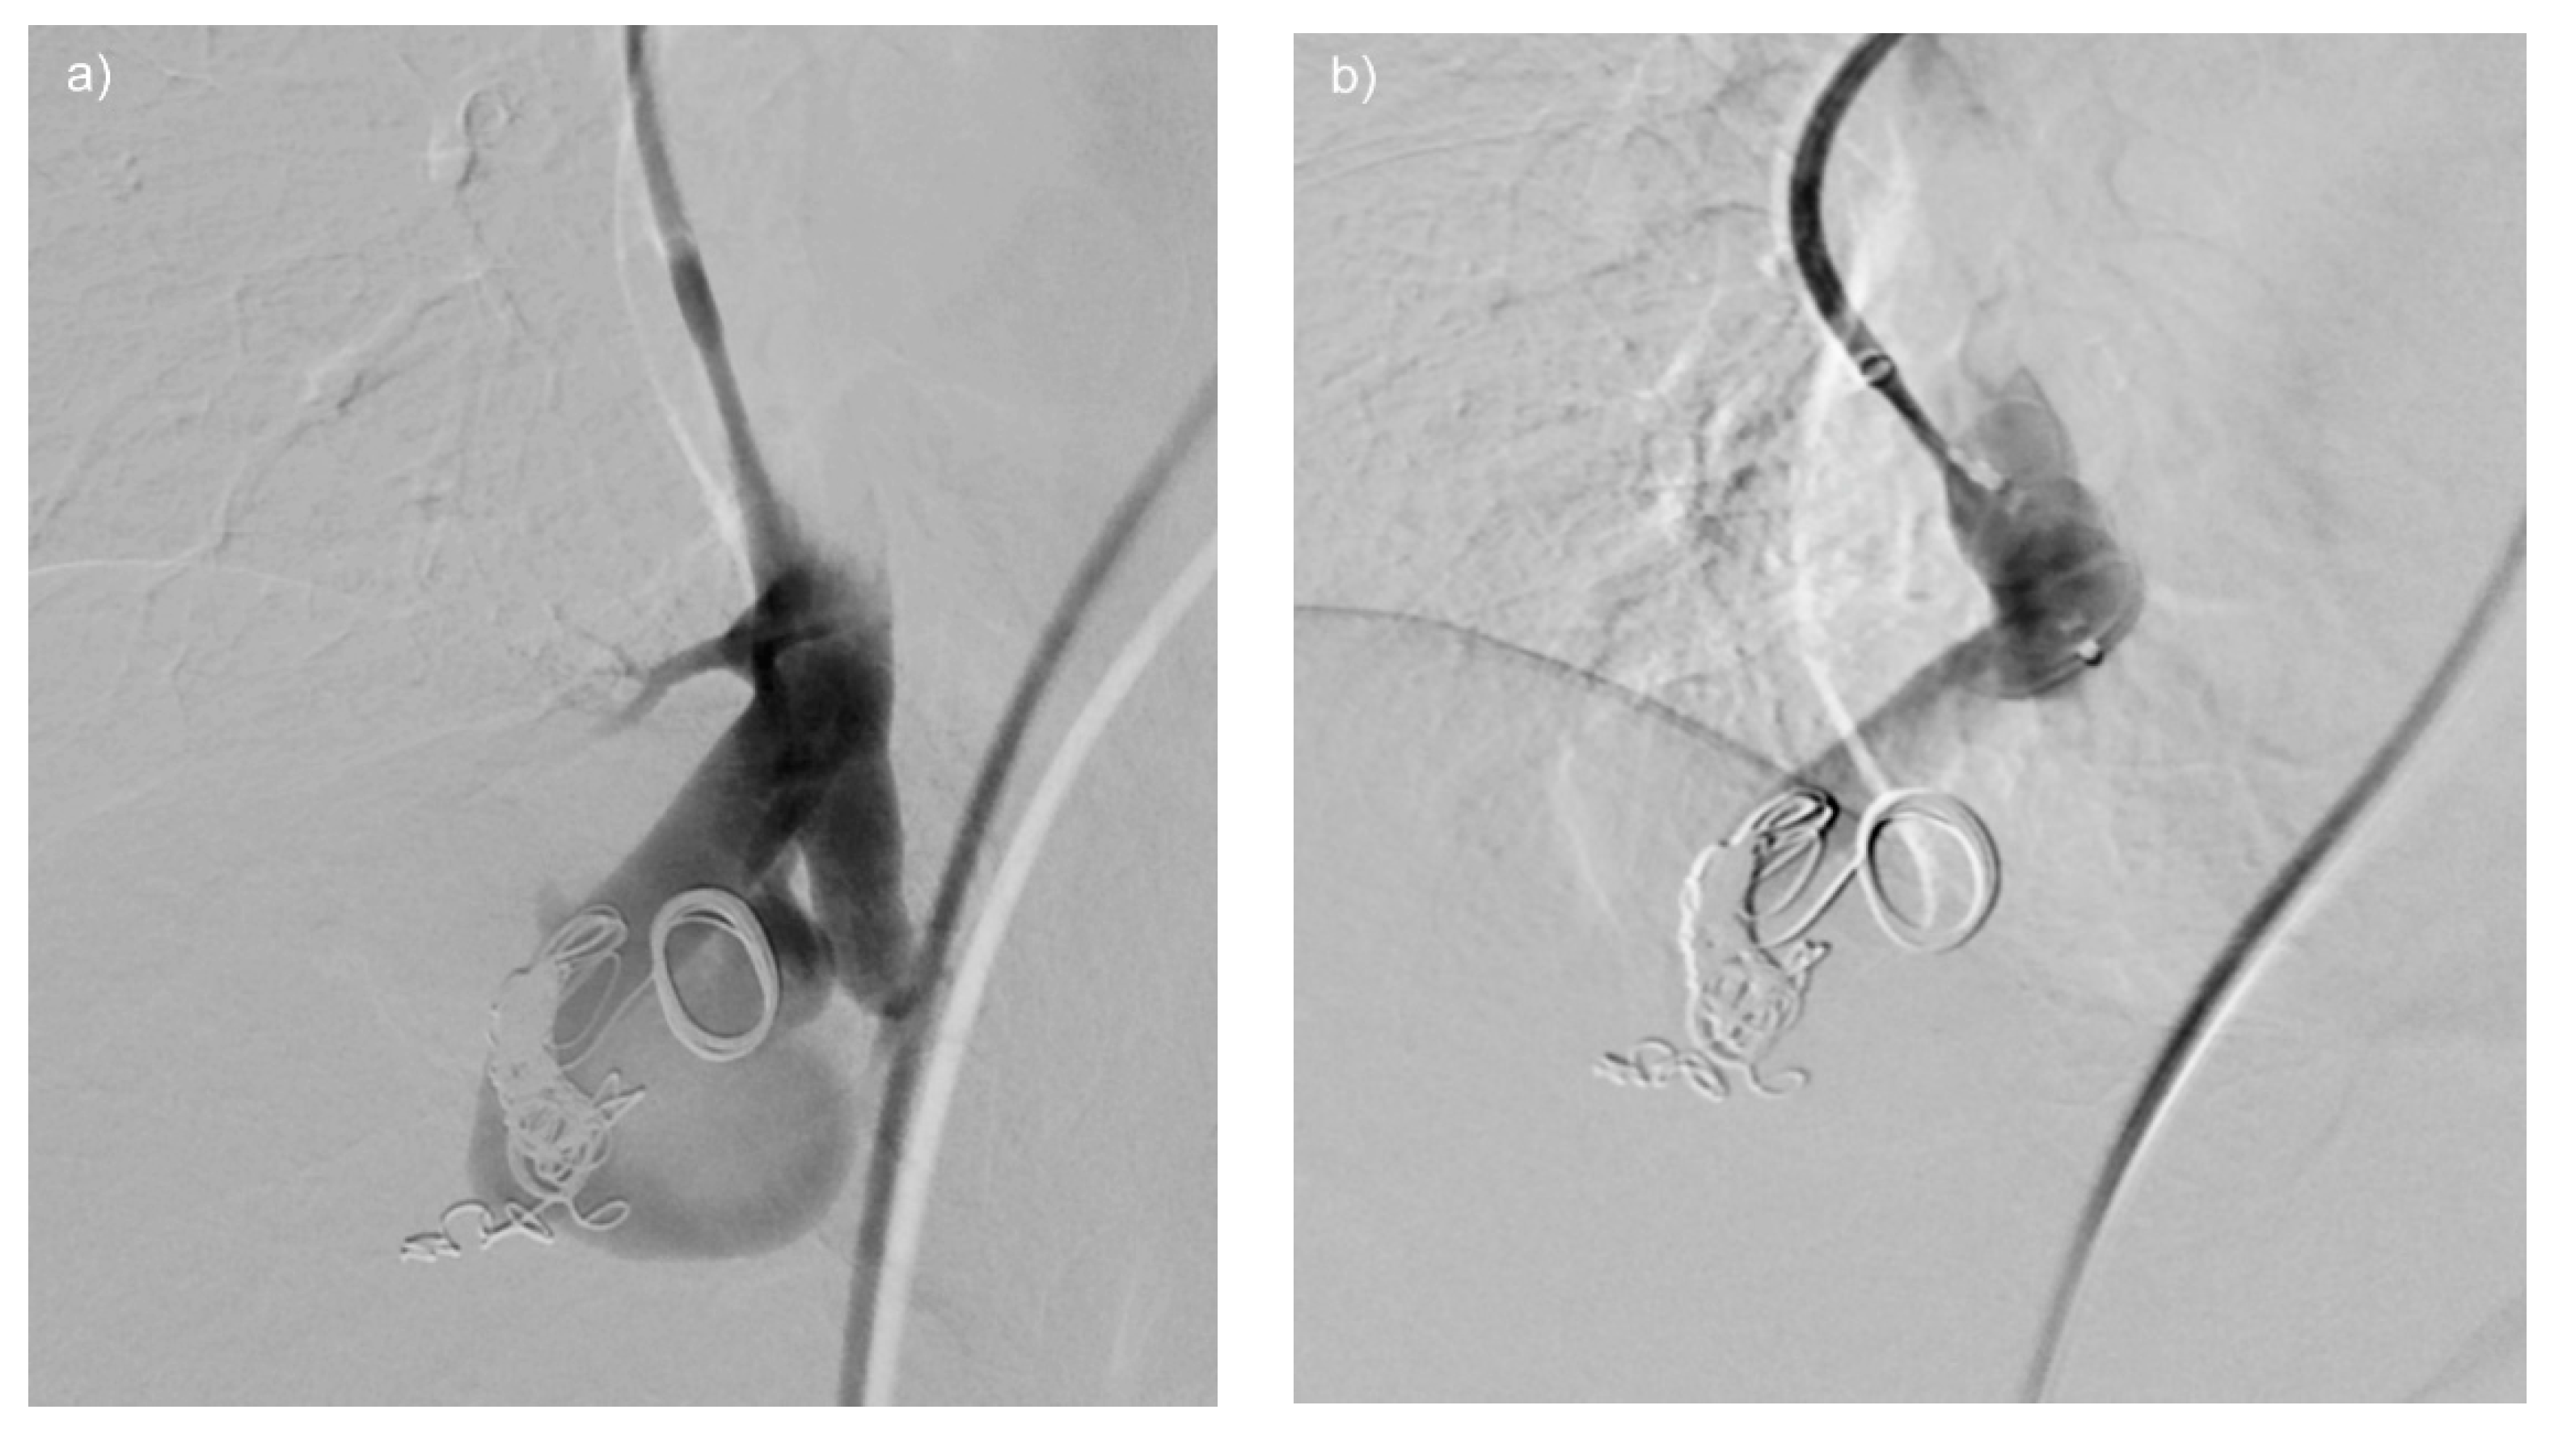

Figure 3. (ac) Re-perfused PAVM after previous treatment elsewhere. Contrast-enhanced MRA (a) shows two large, re-perfused PAVMs (arrows) with early enhancement of the draining vein. In (b) the DSA of one re-perfused PAVM is shown, depicting insufficient dense packing of coils resulting in reperfusion of the vessel. No guide wire should be used, since small thrombi from the coils might be mobilized and lead to systemic emboli. In (c) the second re-perfused PAVM is demonstrated, showing only small coils at the wall of the vessel. Embolization was performed proximal to the treated vessel segment to avoid possible migration of the coils.